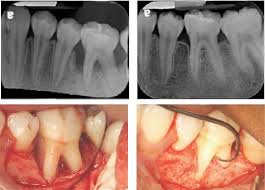

Periodontics is a specialized branch of dentistry that deals with the treatment of gum diseases and the structures supporting the teeth, including the bone and connective tissues. Gum disease, if left untreated, can lead to tooth loss, bone deterioration, and other oral health issues.

• Scaling and Root Planing (Deep Cleaning) – Thorough cleaning below the gumline to remove plaque and tartar buildup.

• Gum Grafting – Surgical correction of gum recession to protect tooth roots and improve appearance.

• Crown Lengthening – Reshaping of gum and bone tissue to expose more of the tooth for restorative or aesthetic purposes.

• Bone Grafting – Strengthening jawbone support for implants or tooth stability.